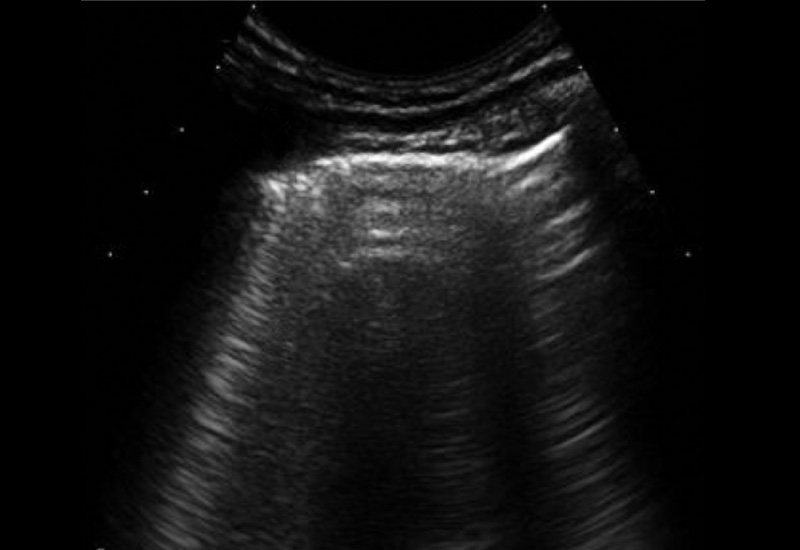

Die Gesamtzahl der B-Linien wurde semiquantitativ wie folgt klassifiziert: 0, normal (≤5 B-Linien); 1, mild (6-15 B-Linien); 2, moderat (16-30 B-Linien); 3, schwer (≥ 30 B-Linien). Im HRCT zeigte sich eine RA-ILD bei 44 Patienten (43,6 %). Anhand der ROC-Kurvenanalyse konnte ein Schwellenwert von >5 B-Linien für die Diagnose von RA-ILD mit einer Sensitivität von 89 % und einer Spezifität von 93 % bestimmt werden. Die Anzahl der B-Linien korrelierte positiv mit dem mittleren Warrick-Score (r=0,836; p<0,001) und negativ mit den LFTs (r= -0,649; p<0,001).

Die Ergebnisse unterstützen die potenzielle Rolle des LUS beim RA-ILD-Screening. Durch die Verwendung eines kurzen Protokolls, das in der klinischen Routine praktikabel ist, zeigte eine B-Linien-Zahl von >5 eine gute diagnostische Leistung für die Diagnose einer ILD und korrelierte mit HRCT- und LFT-Befunden. Wichtig erscheint vor allem, dass ein negativer LUS-Befund eine ILD bei RA-Patienten ausschließen konnte.